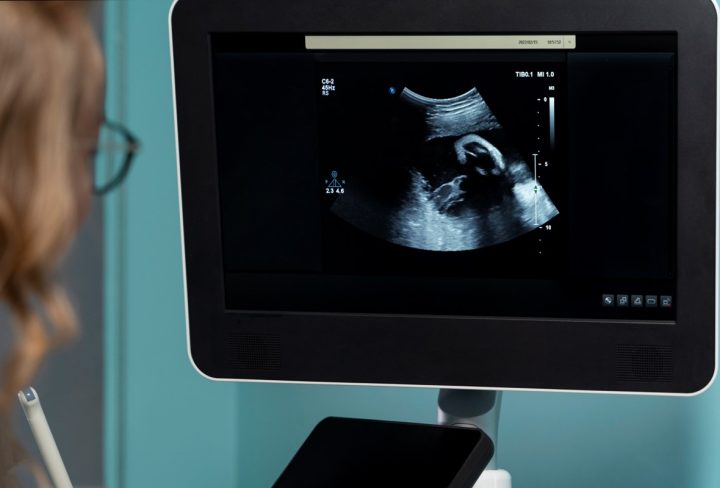

It is a type of ultrasound scan used during pregnancy to produce real-time images, allowing for a more detailed view of the baby’s movements and features.

It also produces the fourth dimension of time, allowing for a video-like view of the baby’s movements.

• The scan usually takes about 30 minutes, and you will be able to watch the entire process on a monitor.